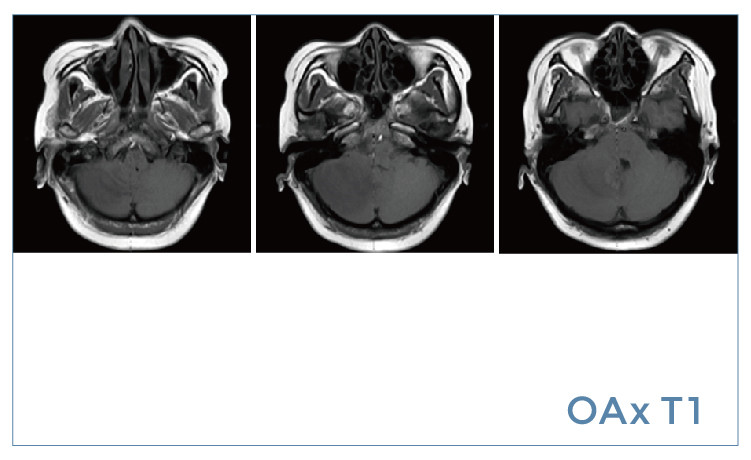

【朗润影像档案】20190802磁共振影像病例结果讨论